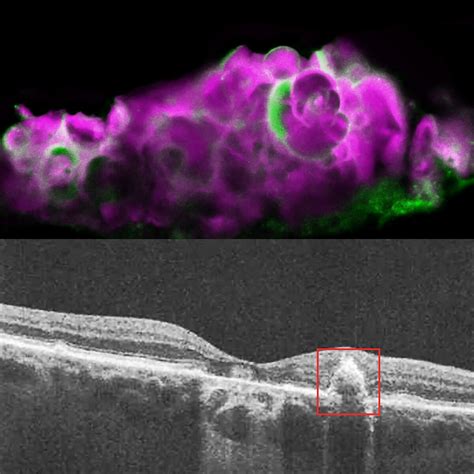

• Corneal Calcification: A more serious condition where calcium deposits form on the surface of the cornea, often appearing as a white, band-like opacity (Band Keratopathy).

• Topical Medications: In cases of corneal calcification (Band Keratopathy), doctors may use chelating agents like EDTA, which help dissolve the calcium deposits.

• Surgical Intervention: For extensive calcification that significantly impacts vision, procedures such as superficial keratectomy may be recommended to polish the corneal surface.